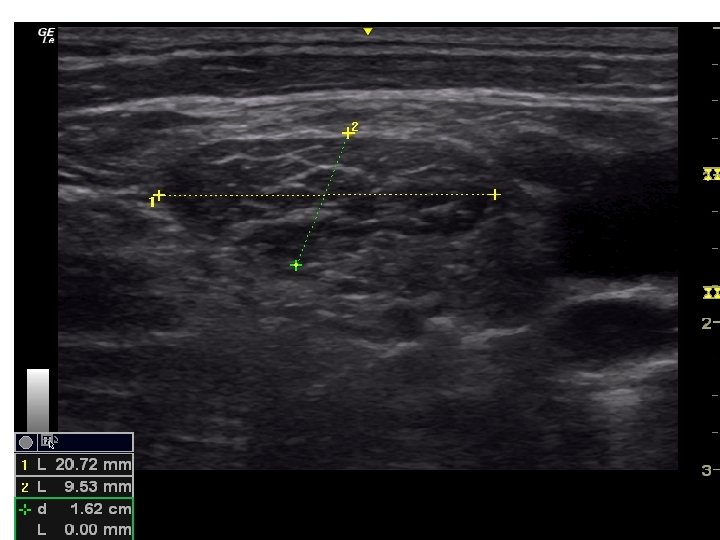

• Tiroid USG • Klinik olarak veya • diğer görüntüleme yöntemlerinde saptanan nodülün tanısının konması için gerçekleştirilir. • USG nodülün – – – – – Boyutu Lokalizasyonu İçeriği Kenar düzeni, Kalsifikasyon varlığı, Ekojenite, Vaskülarite, Şeklinin ve Lenf nodüllerinin değerlendirilmesi için kullanılır.

Sonografik Özellikler, Tahmini Malignite Riski ve İİAB Önerileri Sonografik patern US özellikleri Tahmini Biyopsi için önerilen çap malignite riski >%70 -90 >1 cm Yüksek risk Solid hipoekoik nodül veya solid hipoekoik komponenti bulunan parsiyel kistik nodül: düzensiz sınırlar (infiltratif, mikrolobüle, dikensi), mikrokalsifikasyonlar, boyun enden daha uzun olması, çevrede hipoekoik yumuşak doku komponenti bulunan bozulmuş çevresel kalsifikasyon alanları, tiroid dışına uzanımın kanıtı Orta risk Mikrokalsifikasyon, tiroid dışı uzanım ve uzunlamasına şekil içermeyen düzgün sınırlı hipoekoik solid nodüller %10 -20 >1 cm Düşük risk Mikrokalsifikasyon, tiroid dışı uzanım ve uzunlamasına şekil içermeyen düzgün sınırlı izoekoik/hiperekoik solid nodül veya kenarında uniform solid alanlar içeren kısmen kistik nodül %5 -10 >1. 5 cm Çok düşük risk Ultrasonografik olarak yüksek, orta veya düşük risk tanımlamaları içinde yer almayan spongioform veya kısmen kistik nodüller <%3 >2 cm yapılabilir İİAB yapılmadan izlem de makul bir seçenektir Benign Pür kistik nodüller (Solid komponent yok) <%1 Biyopsi gereksiz( Kist aspirasyonu, semptomlara yönelik veya kozmetik amaçlı planlanabilir. )